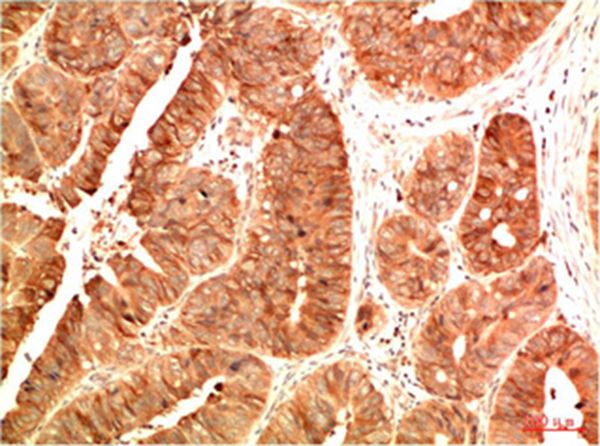

分类: 科研抗体货号: P43824别名: Transcription factor p65 (Nuclear factor NF-kappa-B p65 subunit) (Nuclear factor of kappa light polypeptide gene enhancer in B-cells 3)应用: IHC反应种属: Human,Mouse,Rat